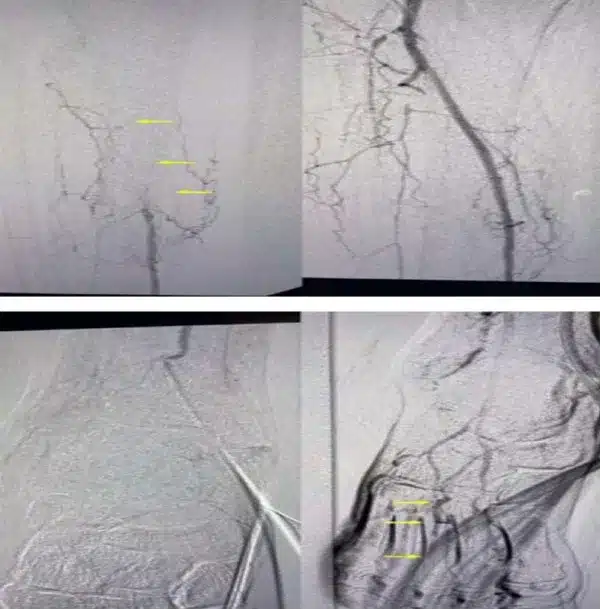

• Smoker with high blood pressure, hyperlipidemia presented with severe left calf claudication that progressed to rest pain of the left hallux

• PVRs showed severe popliteal and infra-popliteal disease; referred for angiography

• Wingman™ used to cross the popliteal; IVL with integrated balloon

• Performed PTA and placed Tigris® stent

• Final angiography shows no residual stenosis and brisk flow